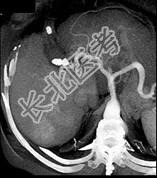

单项选择题男,44岁, 患乙肝多年,现腹痛, 腹胀,AFP增高, 消瘦、乏力,影像检查如图, 最可能诊断为 ( )

A、肝转移瘤

B、肝硬变、肝癌

C、肝腺瘤

D、肝结节性增生

E、肝血管瘤